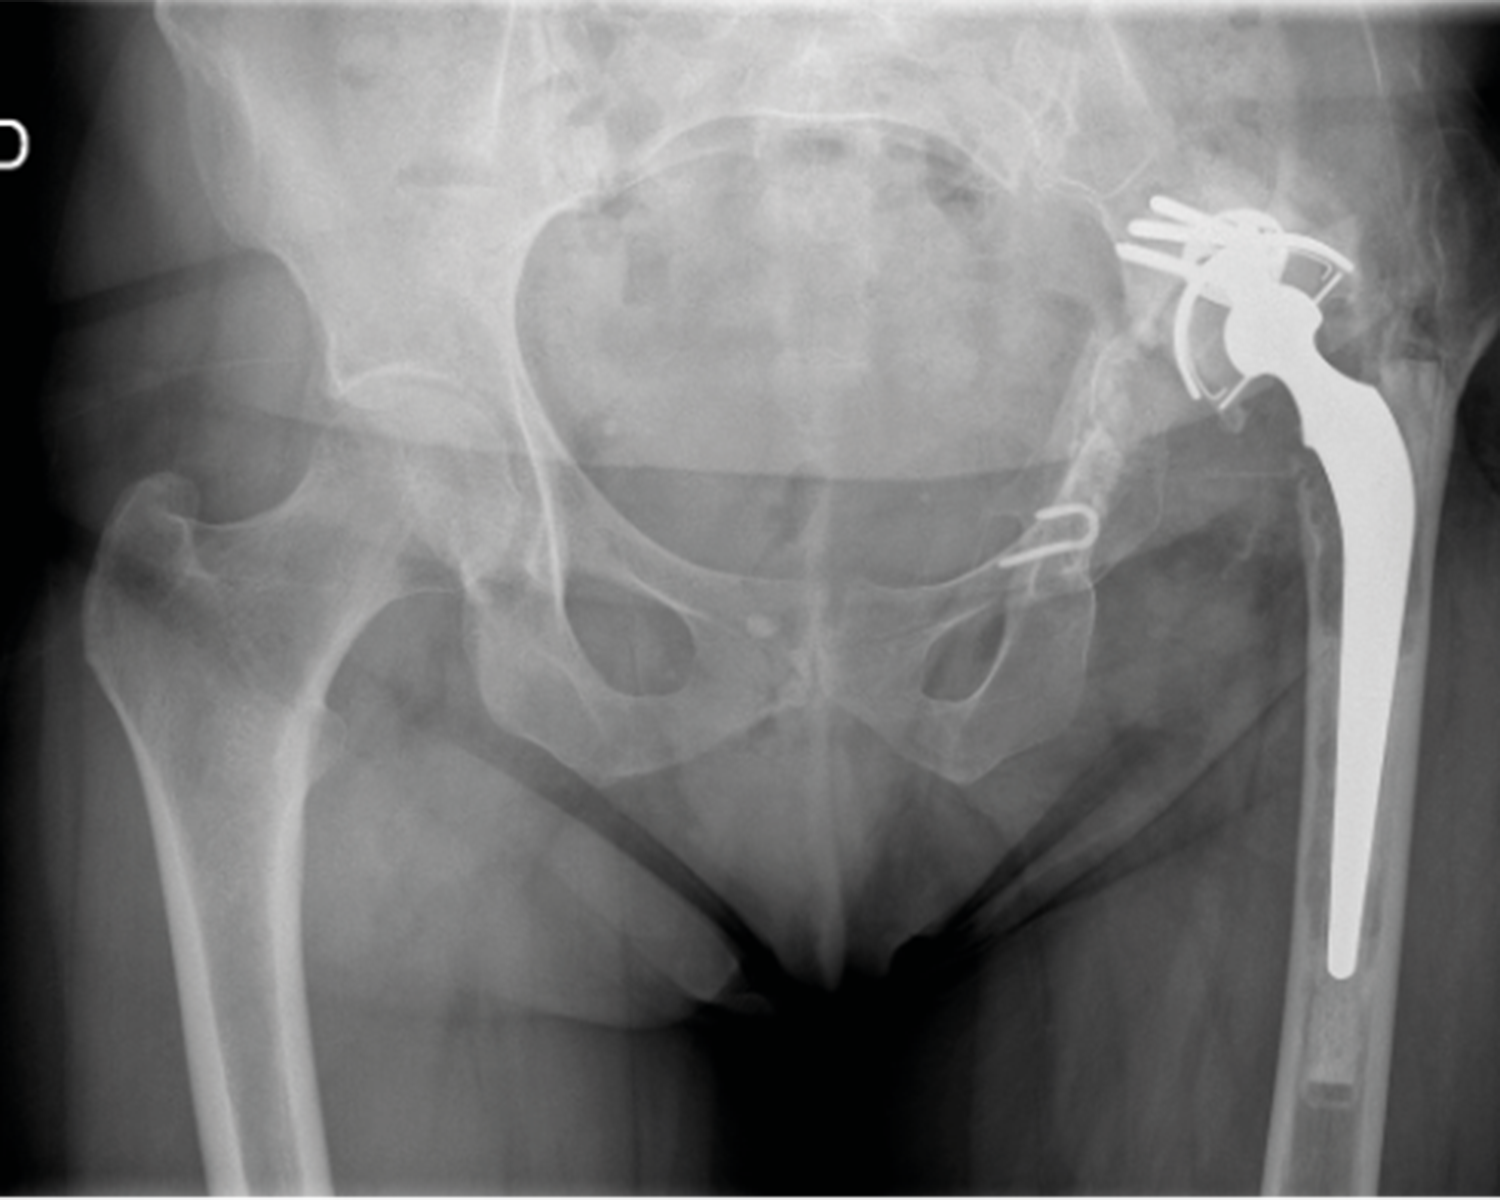

The clinical contributions in this issue address two principal domains. Musculoskeletal infection is examined through a case report on septic arthritis of the native hip caused by Granulicatella adiacens, complemented by a literature review, and a case series investigating surgical options and outcomes in calcaneal osteomyelitis. The issue further addresses revision of total hip arthroplasty, presenting an epidemiological multicentre analysis of 963 patients in France alongside an evaluation of dual mobility systems as a reconstructive strategy in revision settings.